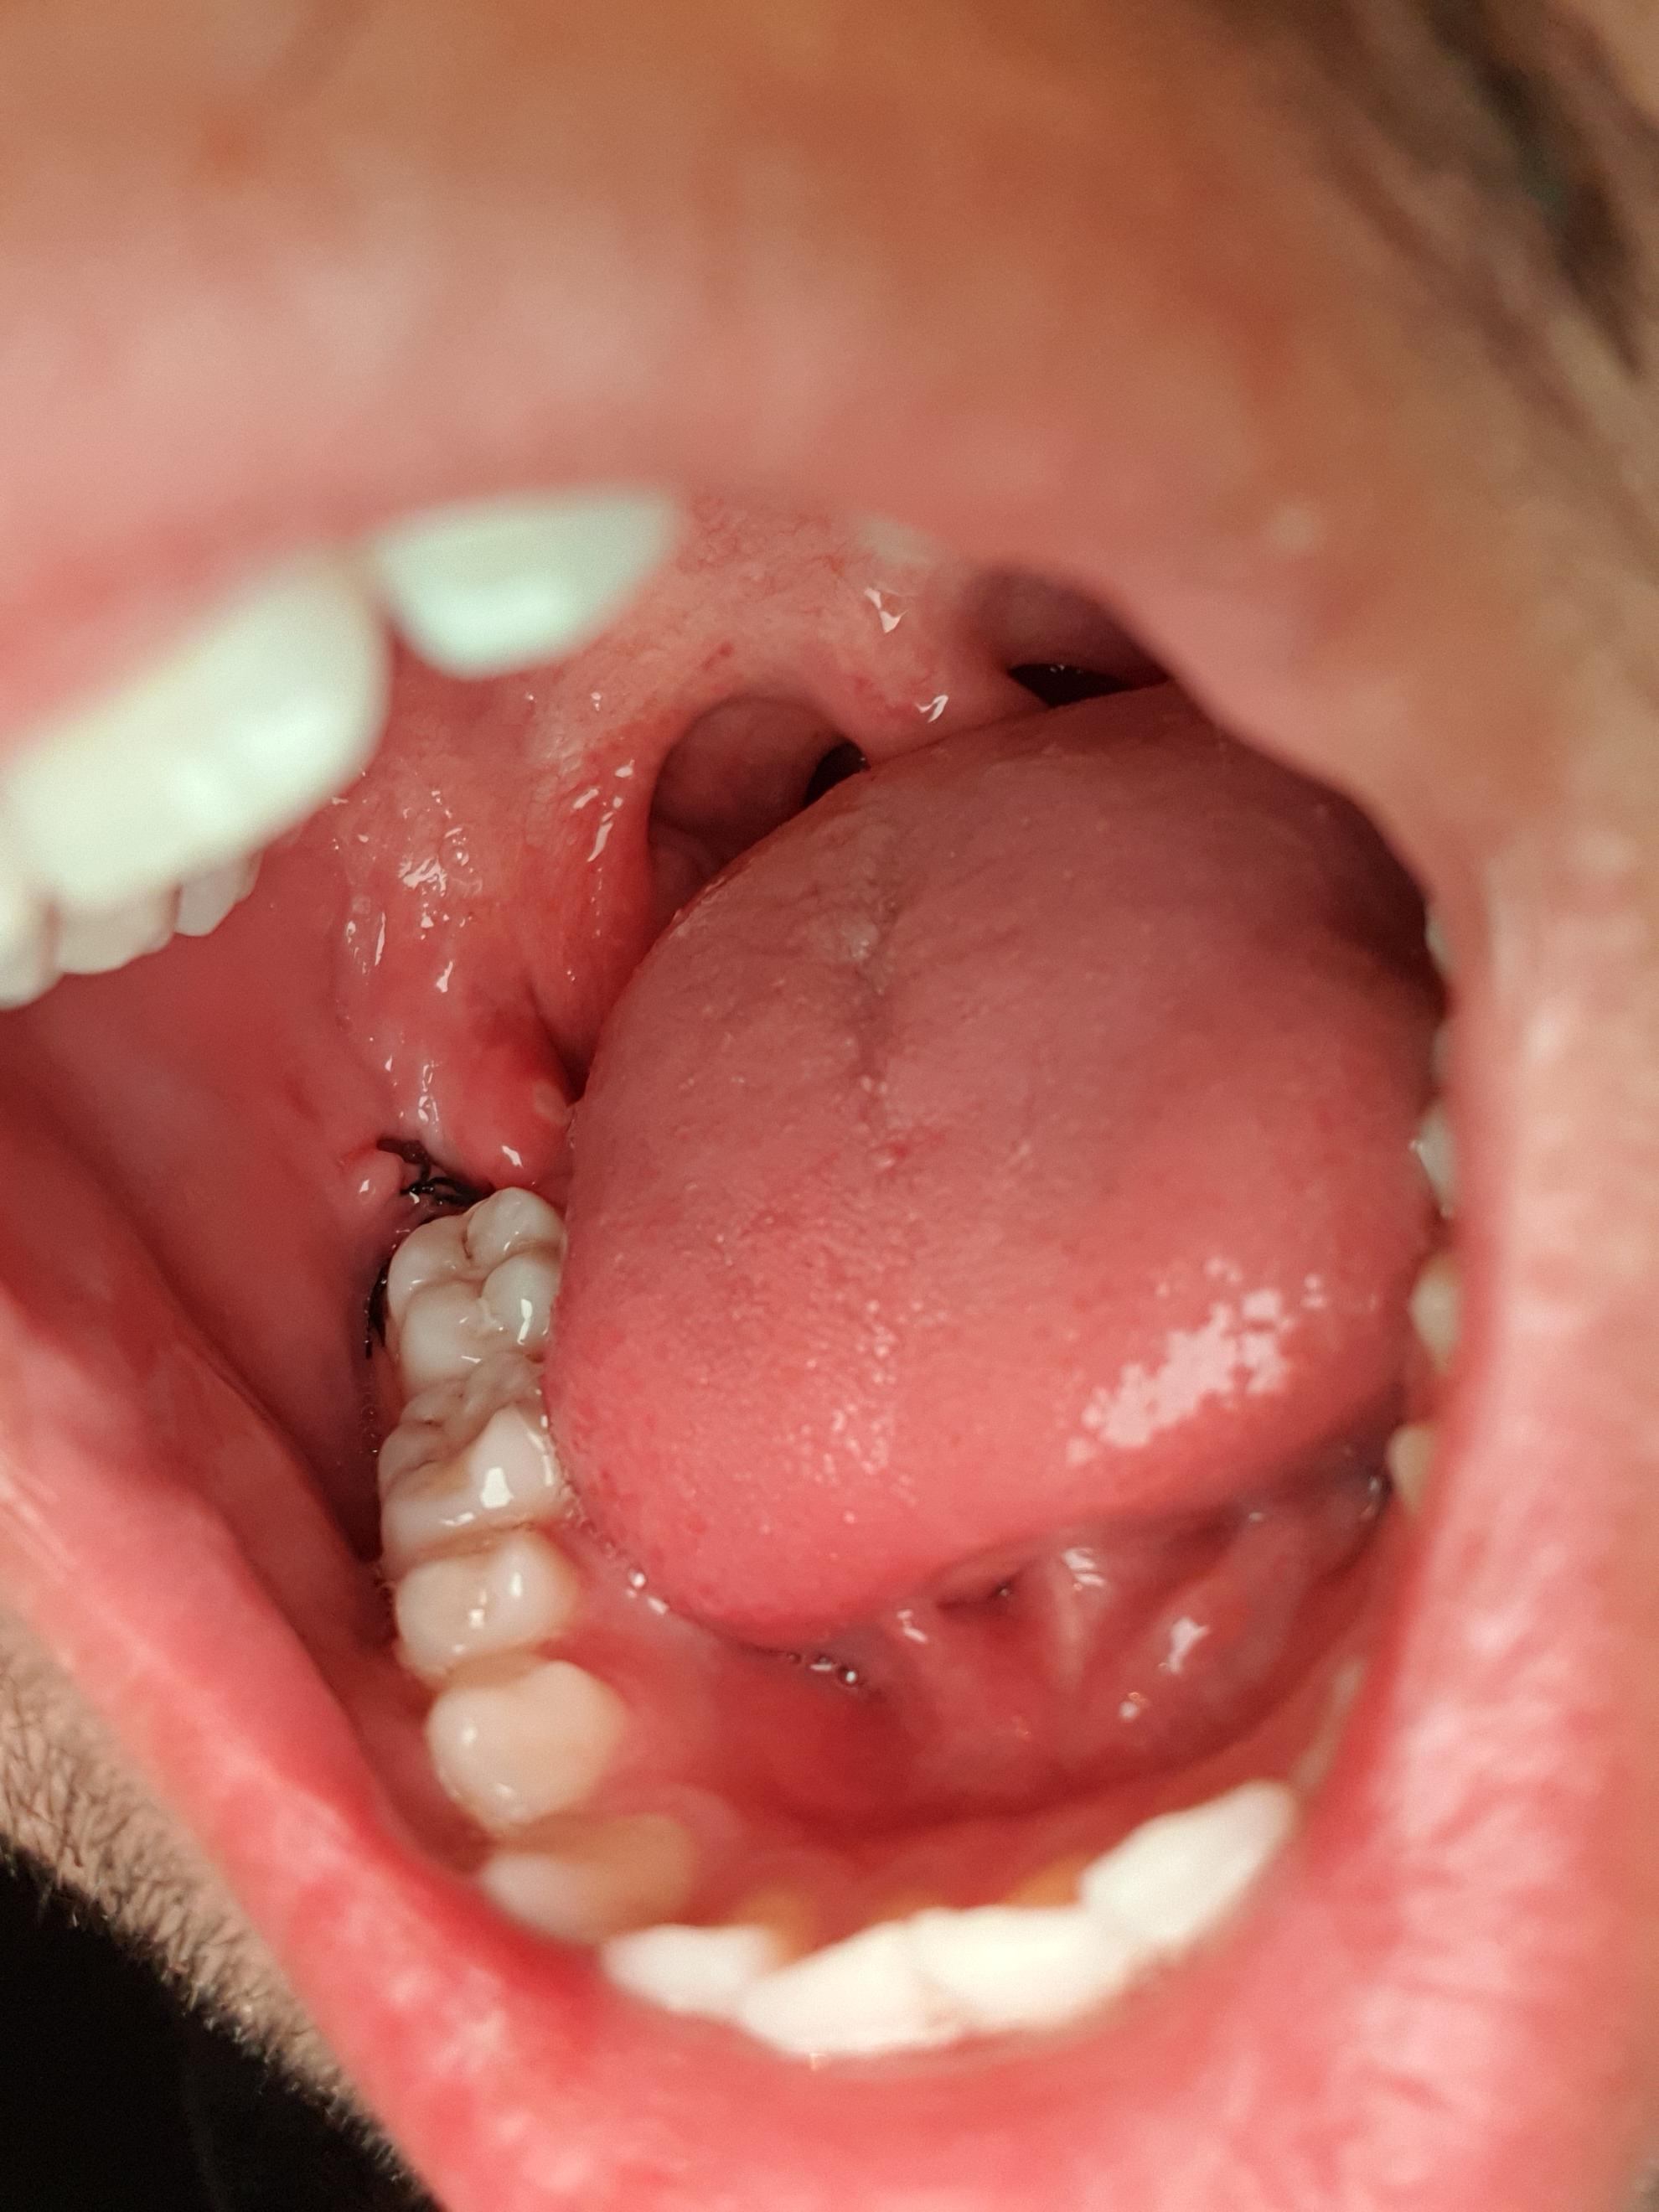

Dort entscheidet der Zahnarzt auch ob die Fäden gezogen werden können. Da eine Weisheitszahnwunde aufgrund der OP auch nach 3 Monaten noch nicht völlig verschlossen ist haben sich dort Speisereste festgesetzt wodurch Du jetzt eine Entzündung hast. Nach etwa zwei Wochen waren die Wunden komplett verheilt die Schwellung war weg und auch die Blutergüsse sind verschwunden.

Mir wurden vor etwas über drei Wochen alle vier Weisheitszähne operativ entfernt. Verhalten nach einer Weisheitszahn OP. Krater entstehen in denen sich uU.

Jetzt hat eine Seite seit gestern wieder eine leichte Schwellung. Das Kauen würde eine zu hohe Belastung für dich darstellen und die Wunde könnte aufgehen. Nicht annähernd so stark wie nach der op aber dennoch sichtbar.